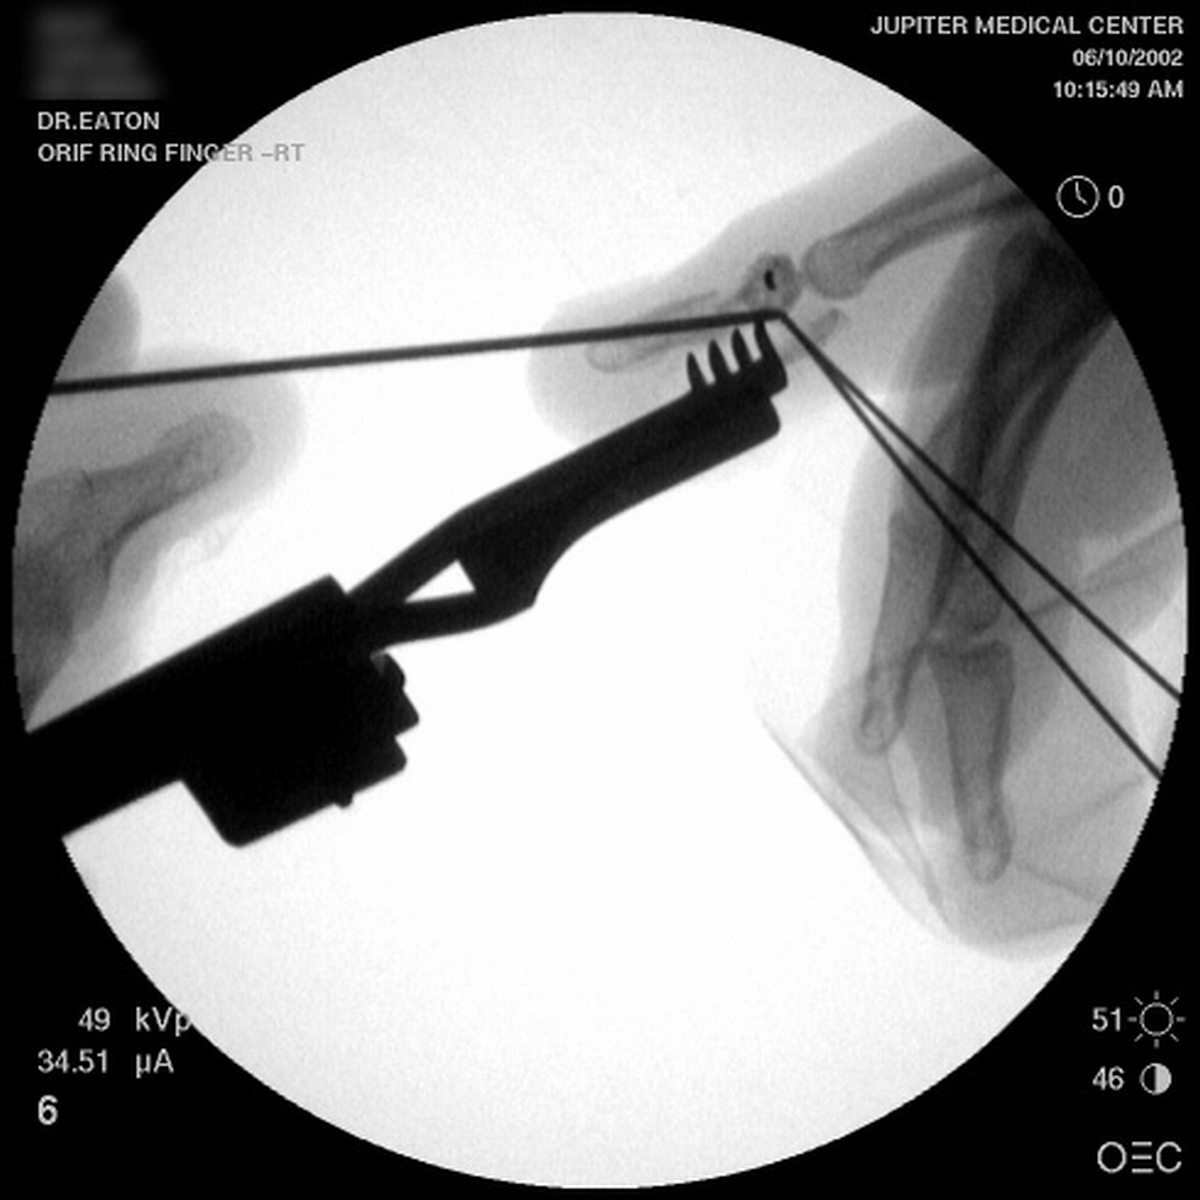

| A midline longitudinal palmar approach was used. This view shows a transverse pin across the dorsal proximal fragment, to be used as a path for interosseous wiring. Additional pins have been placed across each single cortex for later advancement. |

| A wire was passed through the dorsal proximal pin track and then around the palmar pins. After reduction and tightening this wire, the pins were advanced to engage the dorsal cortex. |

| Wiring was used to offset the strong pull of the flexor insertion. |

| All pins were cut below the surface of the skin. |